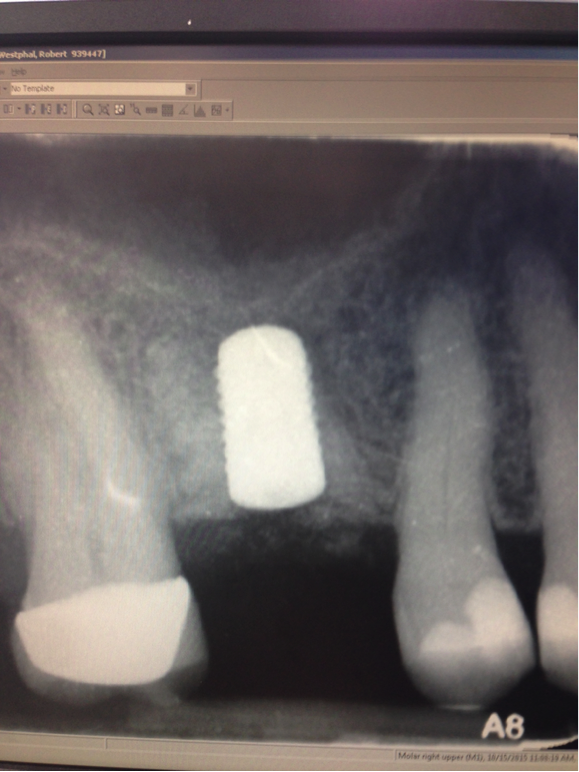

In this case, the patient’s right maxillary first molar had been extracted, and the site was grafted. The periapical radiograph taken after 6 months of healing indicated the presence of dense bone (Figure 11). There was also ample attached mucosa (Figure 12). Impressions were taken, a diagnostic cast was made, and a wax-up of the restoration was placed in the model (Figure 13). To make the radiographic guide for this case, a silicone putty index was created over the diagnostic wax-up, as described earlier. A panoramic radiograph and a CBCT scan (Figure 14) were taken with the radiographic guide in place; the guide post in the index can clearly be seen.

Fig 11. Site No. 3, 6 months after extraction and bone grafting completed.

Figure 11